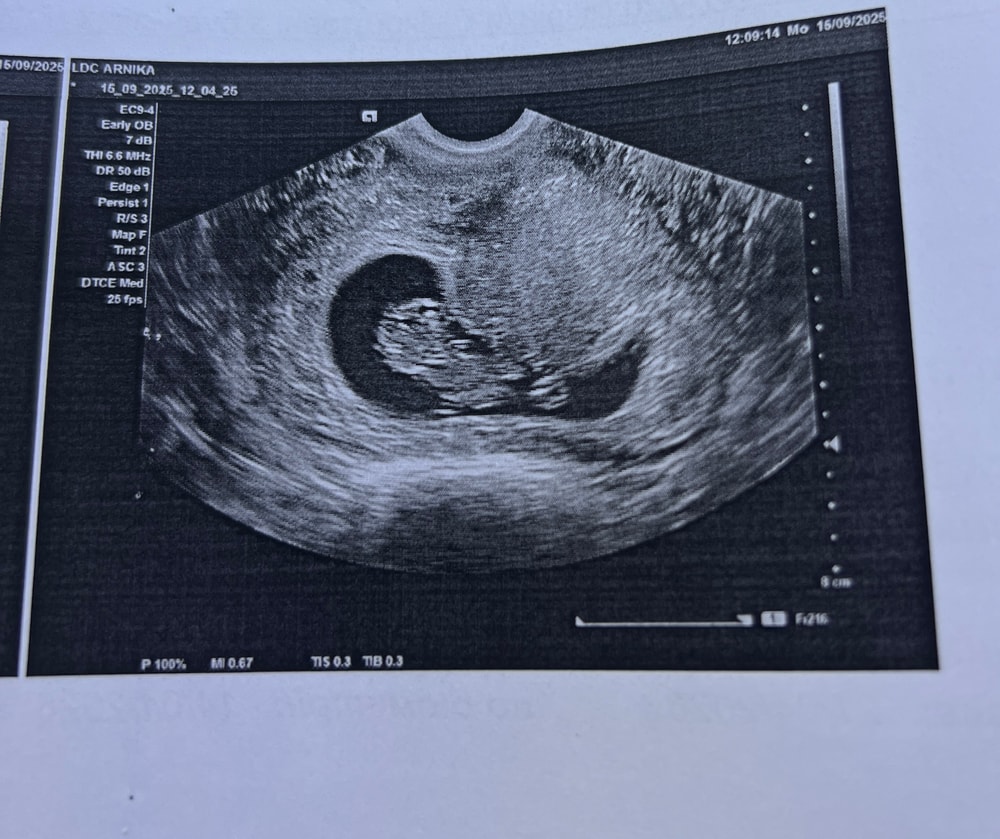

УЗИ 9 недель

Анализы, скринингиВчера была на узи, акушерский срок 9 недель но по узи поставили 10 недель, узист сказала что мы очень крупненькие и не соответствуем 9 неделям😁 и тут я вспомнила как на первом узи нам сказали как все плохо, отстаем на 2 недели и наверное плодное яйцо пустое. Вот, прилагаю фото «пустого» яйца😂

КТР малыша 31,2 мм, толщина эмбриончика 9мм, сб + 166 ударов, структуры мозга хорошие, активничает там в животике😁 так мило было, он крутился как сам хотел, она только начала датчиком водить как он оттолкнулся ножкой, отвернулся от нас и ручку поднял🥹